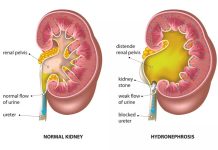

Hẹp Khúc Nối Bể Thận – Niệu Quản (UPJO) Theo Từng Nhóm Tuổi

Bài viết cung cấp cái nhìn toàn diện về bệnh lý hẹp khúc nối bể thận – niệu quản (Ureteropelvic Junction Obstruction – UPJO), phân tích sự khác biệt về sinh lý bệnh, chẩn đoán và điều trị từ trẻ sơ sinh đến người cao tuổi dựa trên các hướng dẫn quốc tế (EAU, AUA, ESPU).

Hẹp Khúc Nối Bể Thận – Niệu Quản (UPJO) Theo Từng...

Bài viết cung cấp cái nhìn toàn diện về bệnh lý hẹp khúc nối bể thận – niệu quản (Ureteropelvic Junction Obstruction – UPJO), phân tích sự khác biệt về sinh lý bệnh, chẩn đoán và điều trị từ trẻ sơ sinh đến người cao tuổi dựa trên các hướng dẫn quốc tế (EAU, AUA, ESPU).